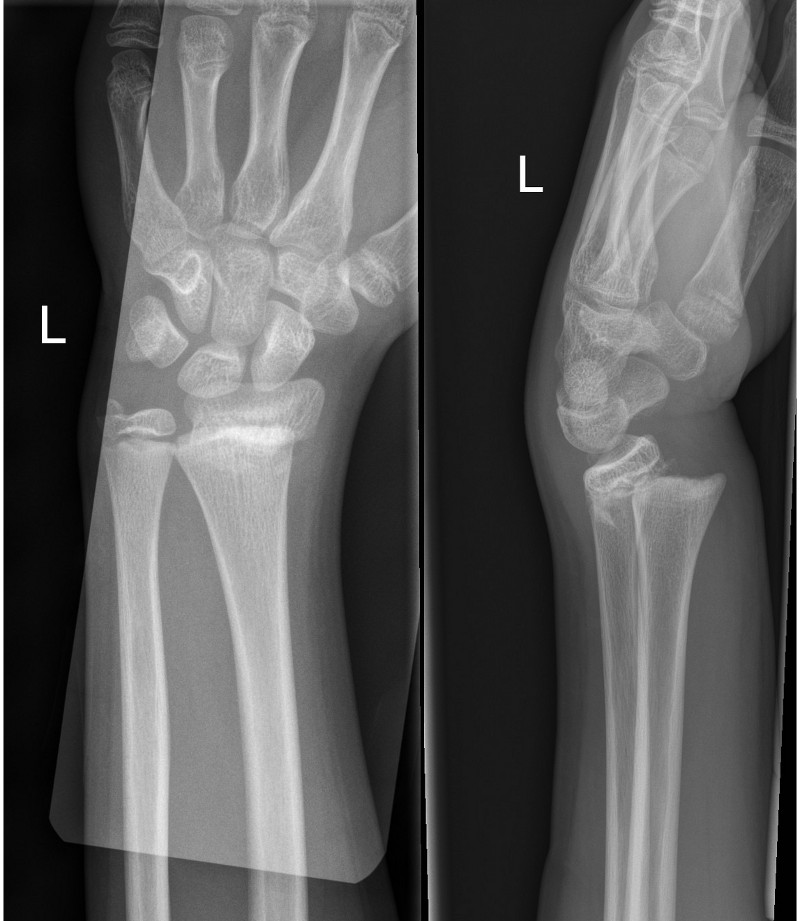

Left image: Transverse fracture of distal radius with 15 degree dorsal angulation

Right image: Completely displaced fracture of distal radius and ulna